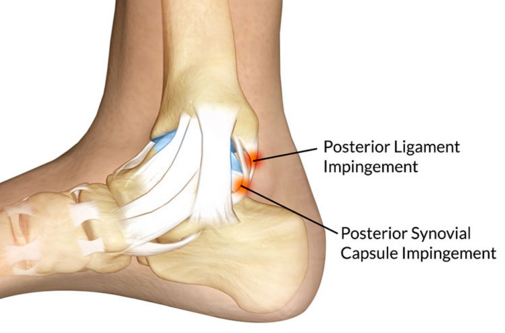

Qu’est-ce qu’un posterior impignement syndrom ?

Douleur et gonflement à l’arrière de la cheville suite à un os trigone (qui est un défaut de la maturation osseuse).